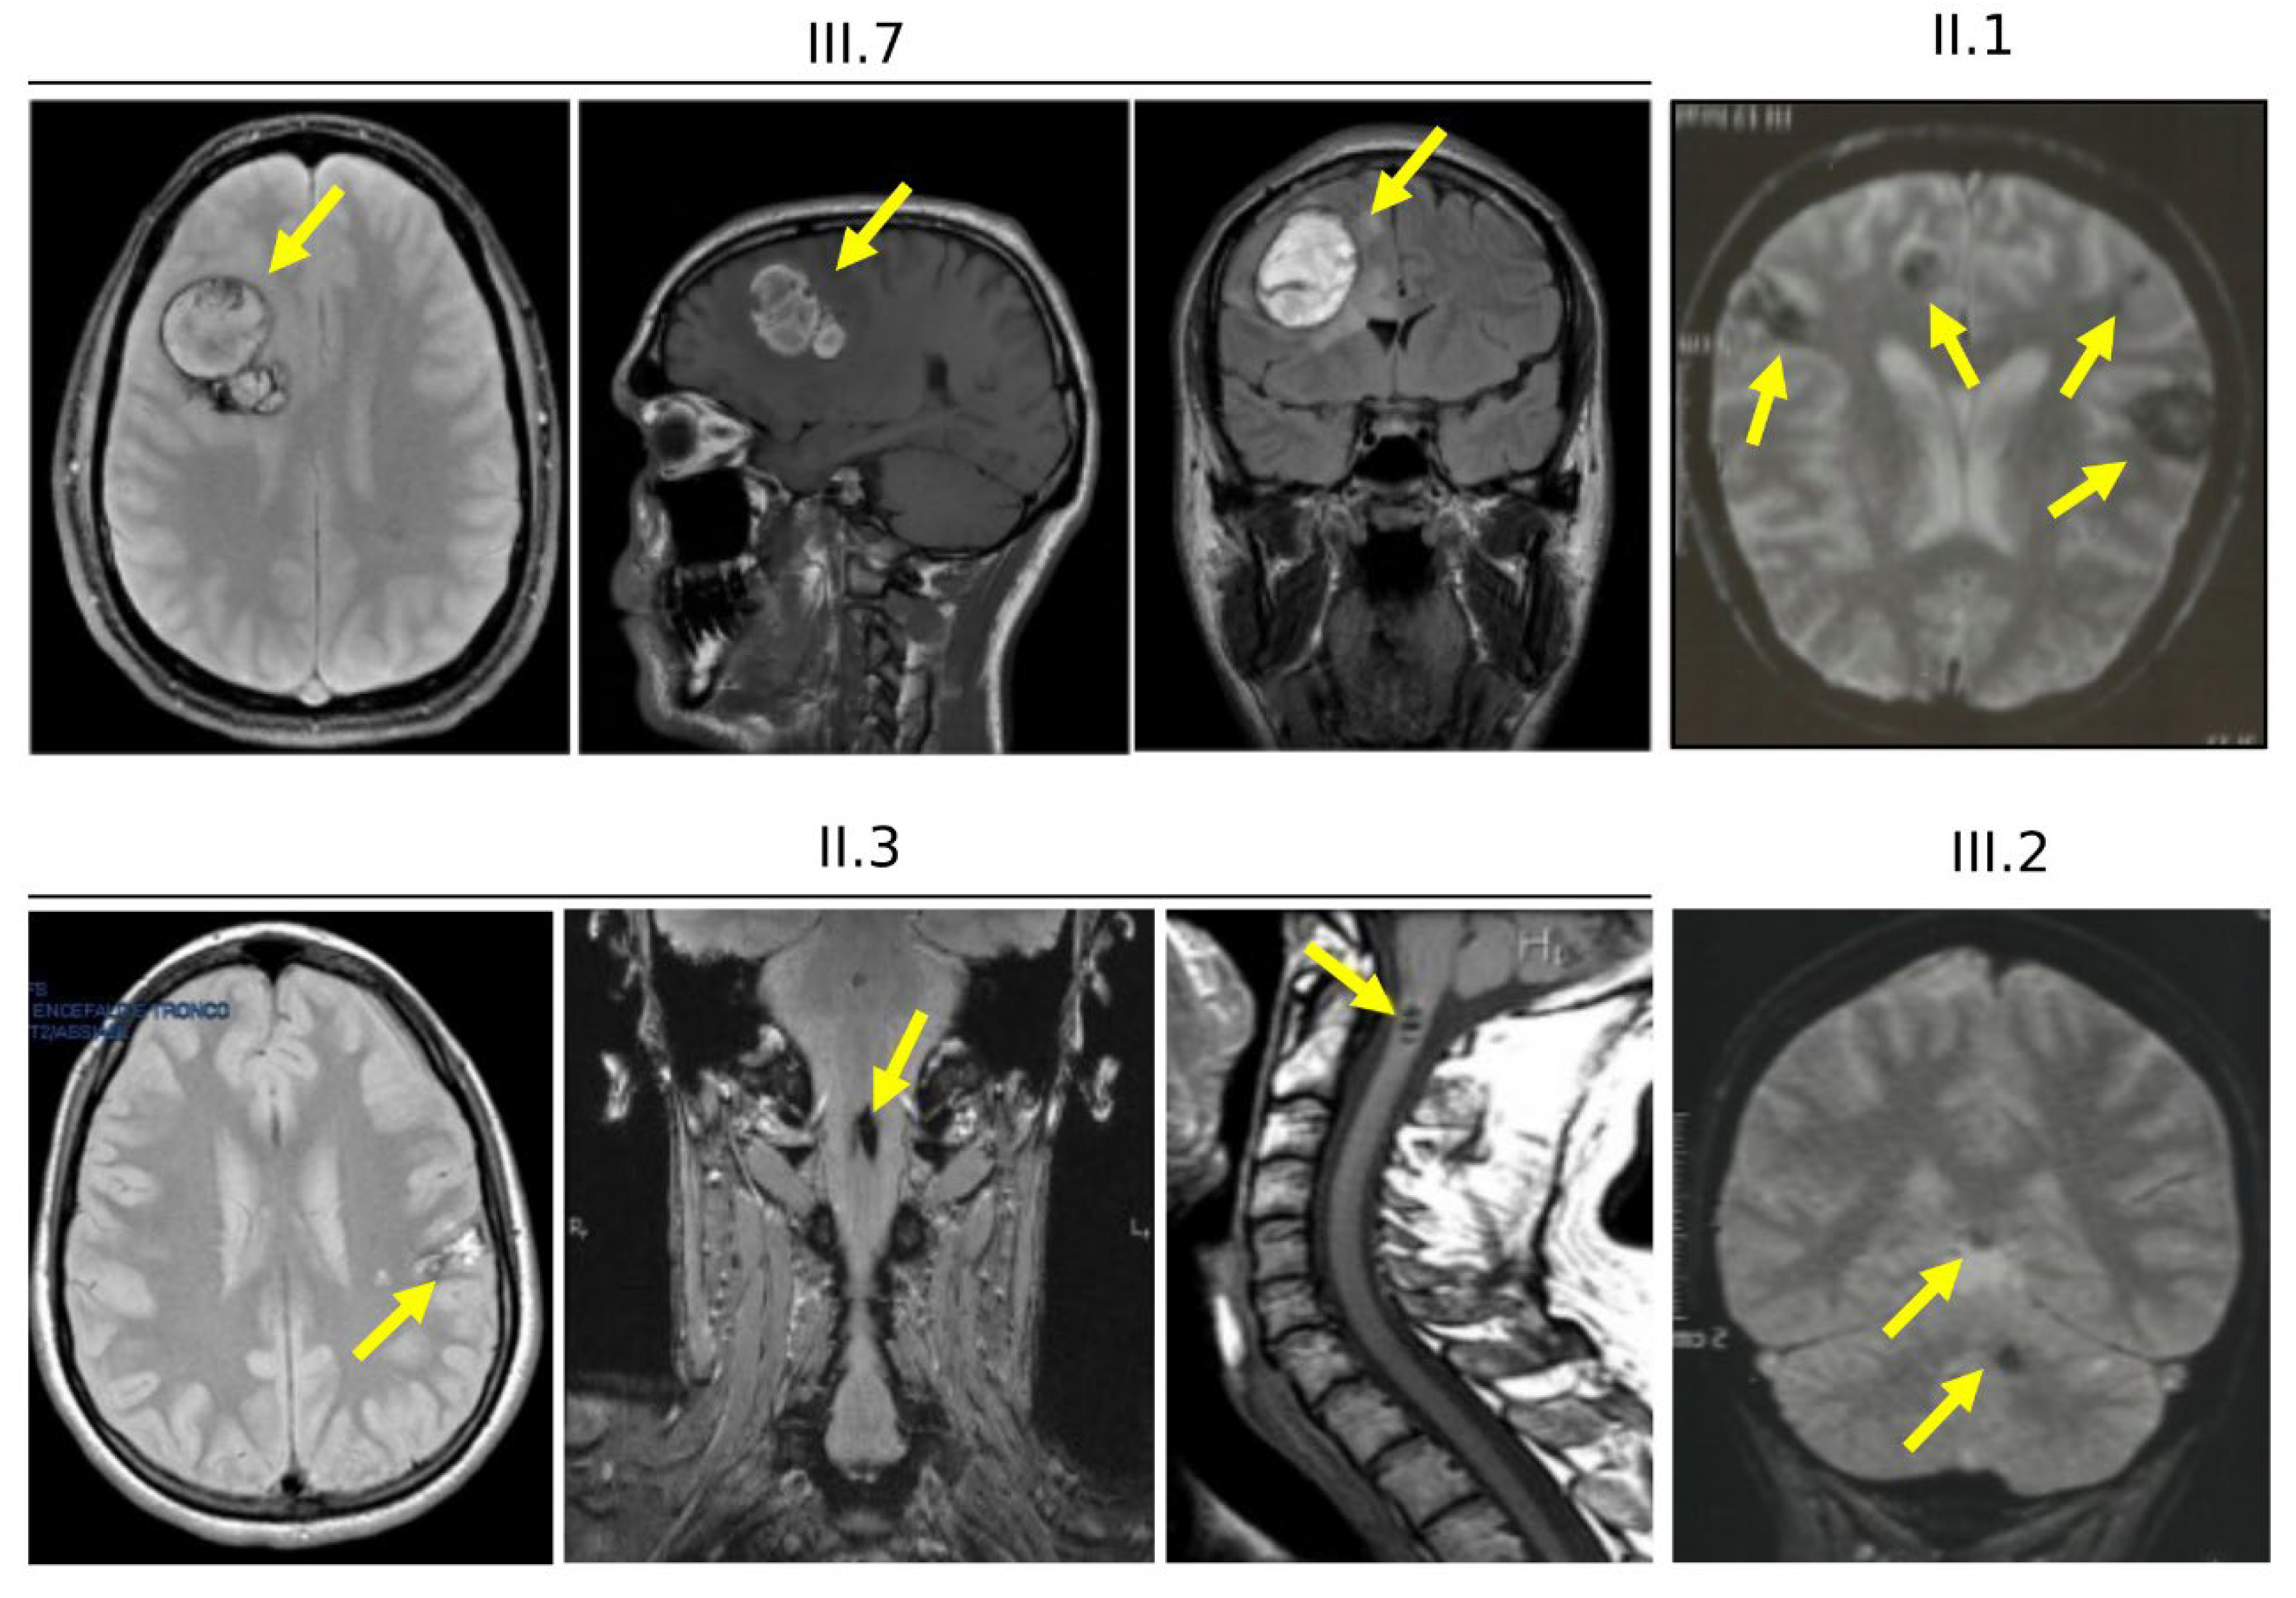

3.4. Clinical Features of Cases Carrying the KRIT1 c.1664C>T Variant (Family 12)

3.6. Clinical Features and Family History of Case #1